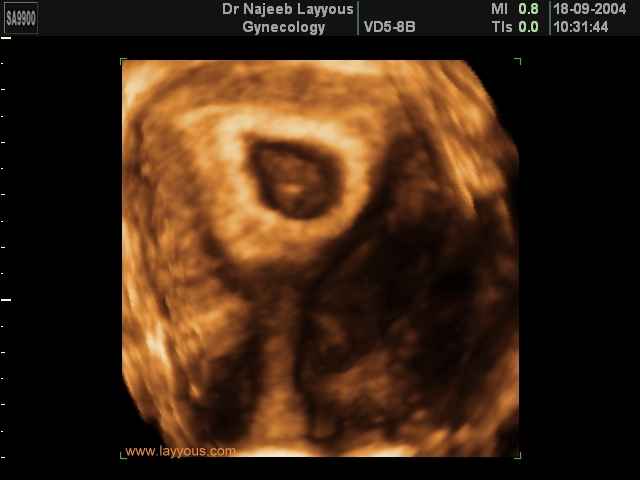

3D First Trimester Ultrasound Scan Photos